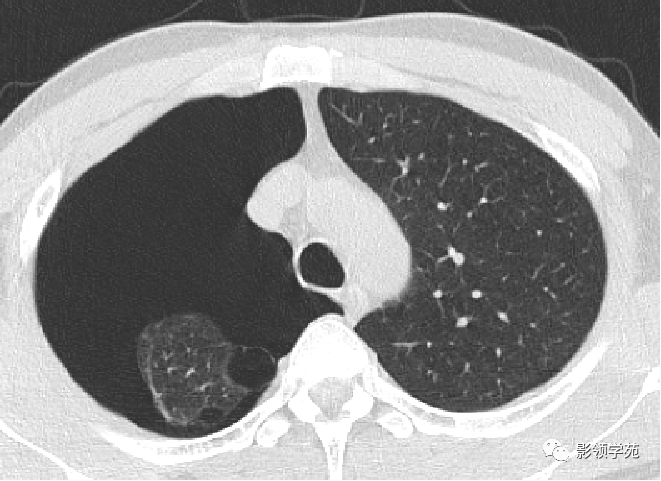

肺大泡的诊断与治疗 肺大疱

肺大泡的症状有哪些 应该如何治疗 每日头条

肺大泡的症状有哪些 应该如何治疗 腾讯新闻

肺大泡的症状有哪些 应该如何治疗 医生一文给你讲清楚

肺大泡的症状有哪些 手术能治好肺大泡吗 到底该如何治疗 雪花新闻